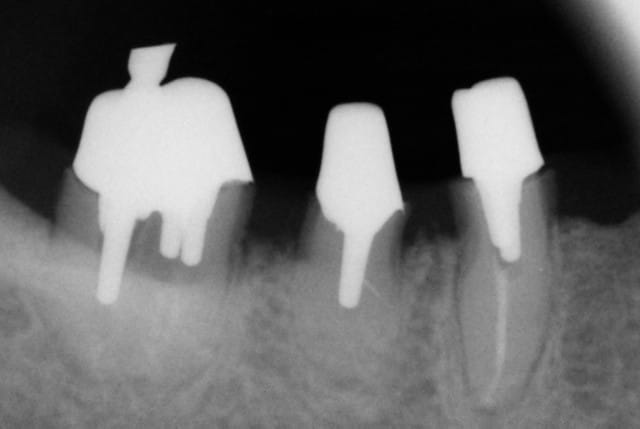

Cette même patiente, pimpante pour ses 90 ans et pleine de gaieté, viens me voir pour son nouvel appareil du bas qu'elle ne supporte pas. Avec surprise, je découvre dessous des chicots abandonnés par son ancien dentiste avec des inflammations gingivales. Radios prises, je lui propose de tenter de les récupérer pour lui réaliser des bridges en remplacement de son appareil, à l'inverse de ce qui se fait habituellement.

La racine résiduelle de la 37 était logée au fond d'un entonnoir gingival au ras de l'os et la 46 était trop délabrée pour la conserver entière. Après quelques séances de gingivoplasties et de tailles, le pari était gagné et les bridges ont pu être scellés, la patiente était radieuse!